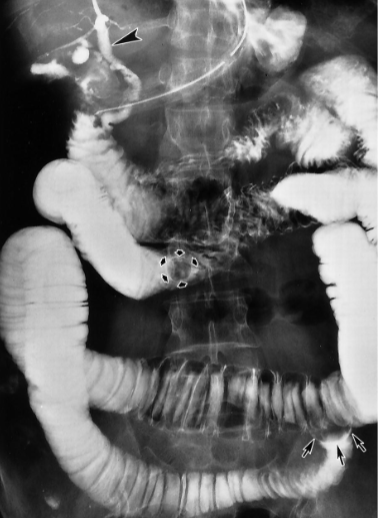

Abdominal Ultrasound most accurate if fasting >8 hrs, as stones are best seen in a distended GB filled with bile

Stones cast shadow + move around

Cholelithiasis

Calcified gallstones in gallbladder, cystic duct, and common bile duct